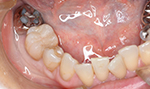

症例2(すきっ歯)

50代の患者さんで前歯の隙間に物が挟まったり空気が漏れる感じがすると訴えておりました。

隙間を埋めてから悩みが解消しましたと喜んでおられました。

回数2回 費用6,0000円

術前

術後